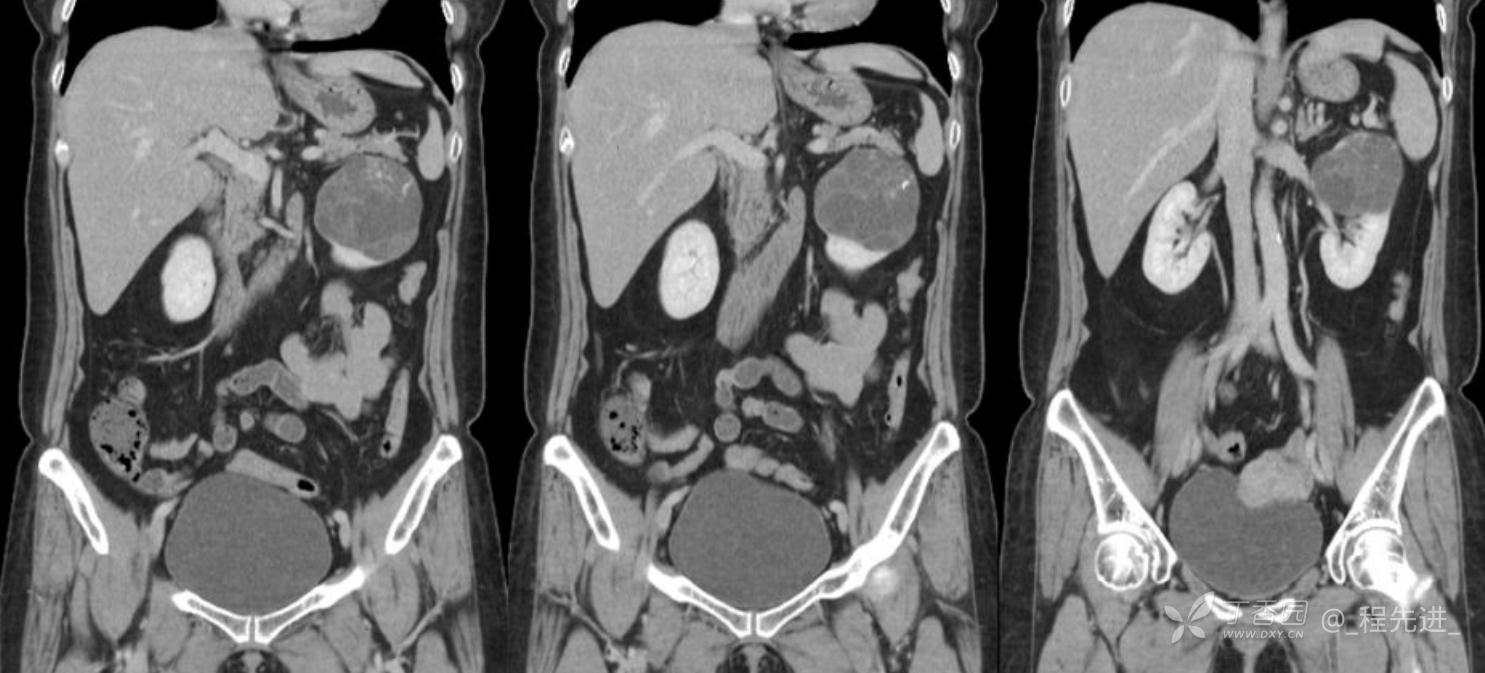

左肾罕见肿瘤病例一例

患者性别:女

患者年龄:53岁

简要病史:反复头昏、头痛5年,再发加重3月

辅助检查:无特殊,输血前检查、生化检查均正常

混合性上皮和间质肿瘤 (1)